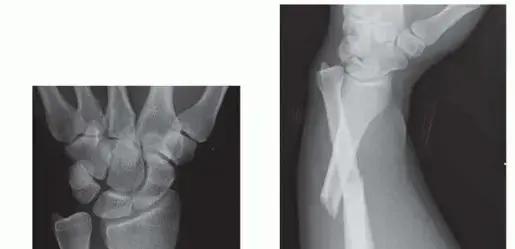

التصوير بالأشعة السينية (X-rays)

تُعد الأشعة السينية هي الأداة التشخيصية الأكثر أهمية وتوفر المعلومات الأساسية. سيتم التقاط عدة صور بالأشعة السينية من زوايا مختلفة (أمامية، جانبية، ومائلة) للساعد والرسغ.

* تحديد الكسر: ستظهر الأشعة السينية بوضوح مكان ونوع الكسر في عظم الكعبرة، وما إذا كان كسرًا بسيطًا، مفتتًا، أو مائلًا.

* تحديد الخلع: تُظهر الأشعة السينية أيضًا ما إذا كان المفصل الزندي الكعبري البعيد مخلوعًا أم لا. يمكن للطبيب رؤية رأس الزند وهو لا يستقر في مكانه الطبيعي بالنسبة للكعبرة. في بعض الحالات، قد لا يكون الخلع واضحًا جدًا في الأشعة السينية، ولكن الكسر في الكعبرة مع وجود علامات غير مباشرة (مثل اتساع المسافة بين العظمتين) قد يشير إليه.